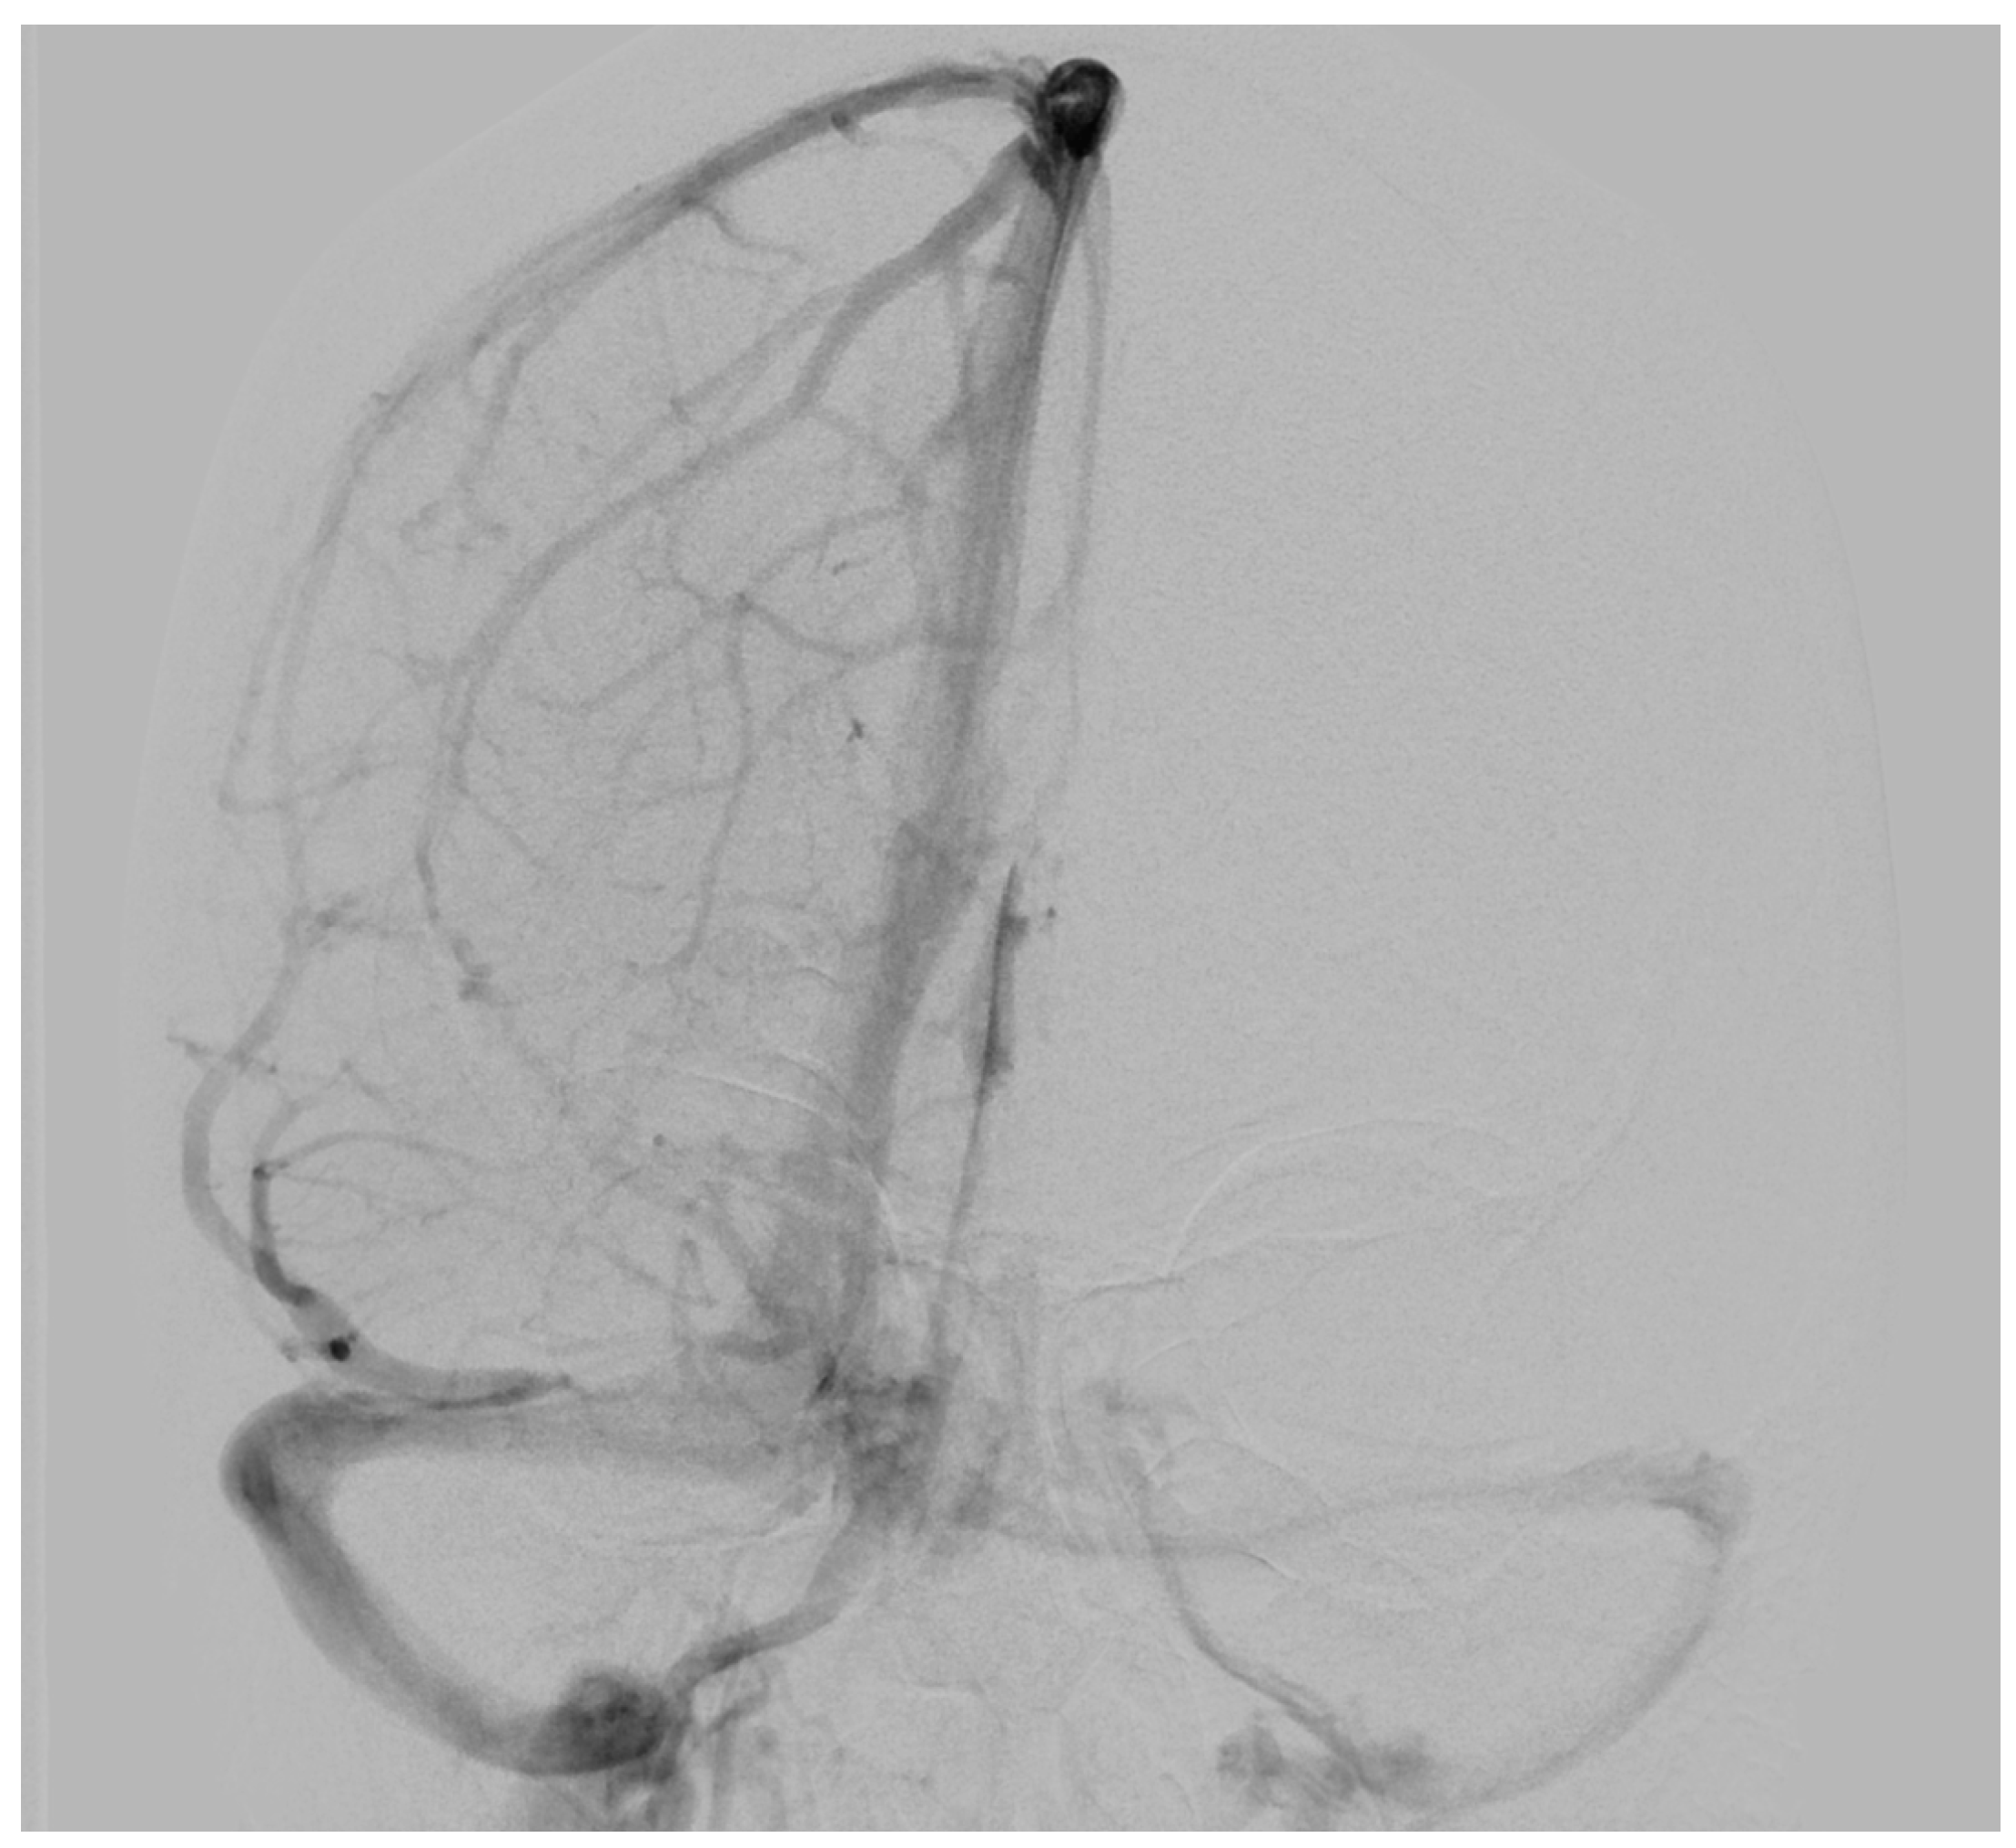

| Our first case | 34 | F | Extra-axial infratentorial on the right | Dizziness, headache, migraine (unrelated to venous hemangioma/no improvement of symptoms postoperatively) | No | 6 years | No recurrence at 3 months, No neurological deficits |

| Our second case | 52 | M | Extra-axial infratentorial on the right | Asymptomatic | No | 1.5 months | No recurrence at 5 months, No neurological deficits |